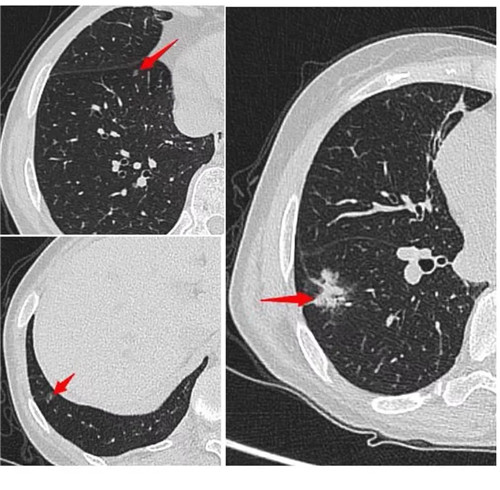

經(jīng)過術(shù)前充分評估,崔凱主任決定一次手術(shù)同期為患者切除雙肺總共六枚結(jié)節(jié)。手術(shù)團(tuán)隊(duì)?wèi)?yīng)用minics肺結(jié)節(jié)三維重建分析及術(shù)前CT引導(dǎo)下錨針穿刺定位等先進(jìn)工具,精準(zhǔn)定位患者雙肺的6枚磨玻璃結(jié)節(jié),其中最大的2cm,最小的0.6cm。

術(shù)前各項(xiàng)準(zhǔn)備完畢,崔凱主任為患者行“單孔胸腔鏡右肺下葉切除術(shù) 淋巴結(jié)清掃術(shù) 單孔胸腔鏡左肺上葉尖后段切除術(shù) 左肺下葉背段切除術(shù) 淋巴結(jié)清掃術(shù)”,一次手術(shù)成功將患者兩側(cè)肺部6枚結(jié)節(jié)全部切除,術(shù)后病理結(jié)果提示六枚結(jié)節(jié)均為早期肺癌。